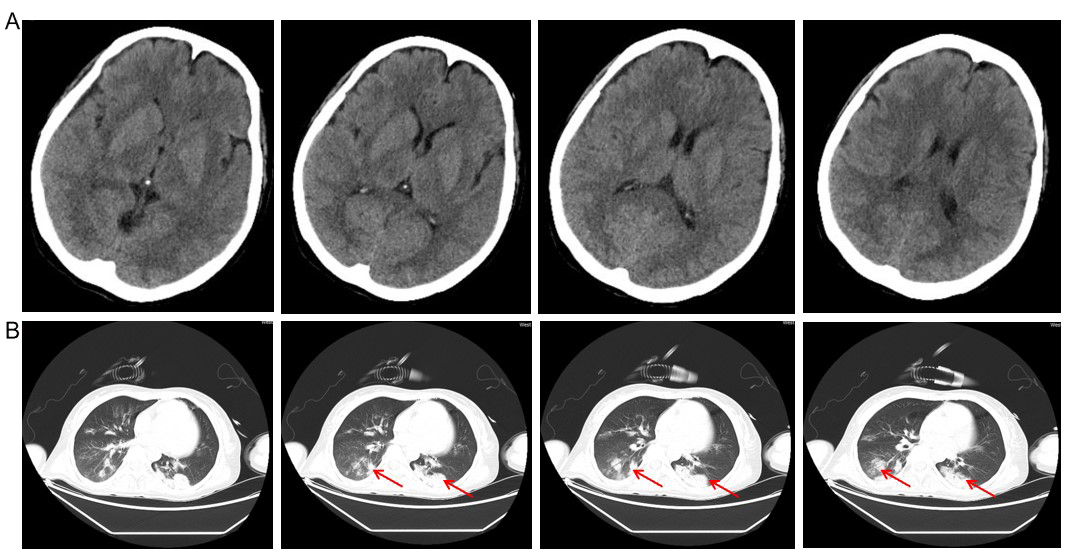

A: 头部CT提示未见异常;B: 胸部CT,箭头所示双肺感染 图 1 头胸部CT平扫情况

本例患者中毒特点是病程进展迅速,中毒1 d后即出现意识障碍,与郑武洪等[1]报道病例虽相似却又有所不同,不同处在于后者案例含有甲氨基阿维菌素,患者意识障碍为甲氨基阿维菌素的中枢神经系统损害作用所致[4]。本案例虽早期也出现意识障碍,可头部CT检查却无异常发现(图 1A),患者短时间内出现意识障碍其具体原因不清,可能与靶器官肝脏受损血氨升高致肝性脑病相关,也可能为丁醚脲潜在的中枢神经系统损害相关所致。目前,丁醚脲是否具有中枢神经系统损害作用尚无相关研究。本案例中毒2~4 d后即出现心脏、肝脏、肾脏、凝血功能、造血功能等多个器官功能障碍(图 1~3),其中尤以肝功能损害为重(图 3)。研究发现,甲氨基阿维菌素和丁醚脲混合中毒可在病程早期出现休克、多器官功能障碍、代谢性酸中毒等,肝酶可在中毒后第3天升高达高峰[1],此案例与之类似。但罗醒政等[5]研究发现,肝酶异却多在中毒后第4~5天达峰,其原因可能与丁醚脲独特的肝脏损害机制有关[6],有待进一步对其具体肝毒性分子机制进行深入研究。本例患者病程早期即出现高乳酸血症(图 2A),一方面,可能与丁醚脲具有抑制有氧代谢作用相关[7],致使三羧酸循环代谢通路异常,乳酸堆积。另一方面,可能为丁醚脲的肝毒性作用,肝功能受损后乳酸清除障碍。机体严重感染会导致造血抑制,进而引起血小板减少[8],血小板减少的程度可间接反应炎症反应的危重程度[9]。本病例患者在起病第3~4天炎症反应达高峰(图 2B),可能与患者昏迷误吸致吸入性肺炎肺部感染加重有关(图 1B)。受炎症反应影响,血小板也在此时间段内降到最低。此外,也可能为丁醚脲中毒本可导致血小板减少[10]。病程后期血小板逐步回升(图 2C),一方面,患者肺部感染得到了控制。另一方面,血液灌流及血液净化及时清除了毒性成分及炎性因子。除了肝功能、有氧代谢及造血功能受损以外,心肌及凝血功能也有受损(图 2DEF),并且表现出与上述靶器官受损类似的特点。部分原因为此阶段炎症瀑布反应所致,也可能是丁醚脲对心肌及凝血功能的损害作用导致,其具体机制不清,有待进一步研究。